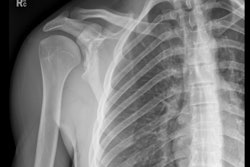

- Whole-body contrast-enhanced CT is the default imaging procedure of choice for severely injured patients.